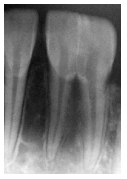

Em uma radiografia periapical

de um indivíduo desconhecido,

solicitada para fins de identificação

odontolegal, observa-se um dente

incisivo inferior com duas raízes

separadas e com canais radiculares

independentes; contudo, apresentando duas coroas fundidas parcialmente, ilustradas na imagem

abaixo.

Com base nesses achados, assinale a alternativa que descreve corretamente as alterações dentárias observadas.